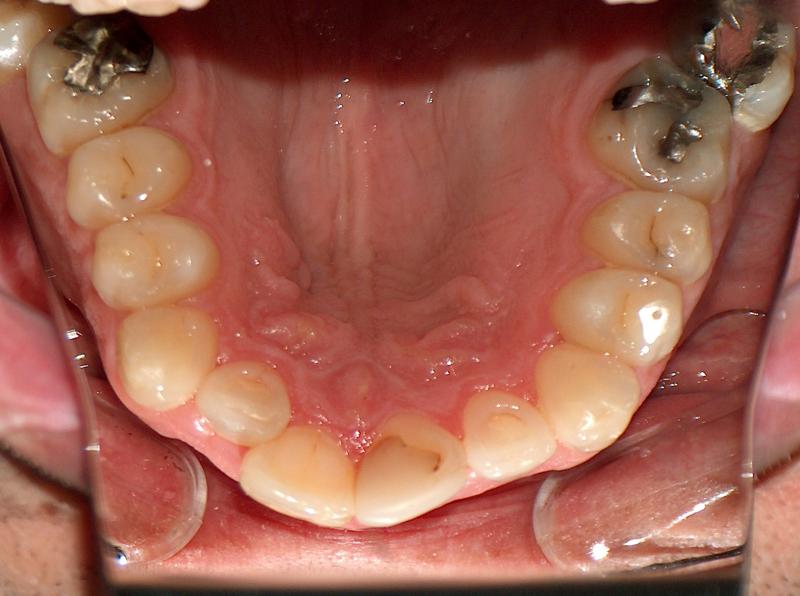

Steve N.

Invisalign Case

INVISALIGN, 16 months, 2 series of aligner to correct the anterior cross bite, to intrude the over erupted and extremely crowded lower incisors. COSMETIC DENTISTRY, leveling of incisal edges, gingival tissue contouring, and cosmetic bonding.

Cosmetic Dentistry, Mid-line Asymetry, Severe Crowding